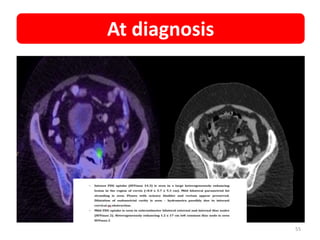

55

At diagnosis

56

• NAME • UMR •Diagnosis • Cancer cervix with common iliac node • RADIATION • EBRT –VMAT SIB 50Gy/25# -56Gy/28# • REGULAR FOLLOW UP • Post RT 3month - CR • Presented with • DVT and left leg pain • PET • Nodal recurrence same area • Planned SBRT • 30Gy/5# • PET POST SBRT 3M • Decreased SUV value • Now • Follow/up Case details 54

• 55.

• 56.